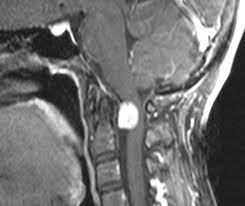

MR; omurganın primer tümörlerinin tanı ve değerlendirilmesinde tercih edilecek bir yöntemdir. Avantajları; yumuşak doku görüntülemesinin iyi olması, multiplanar görüntü elde edilebilmesi, nöral bası veya infiltrasyonun değerlendirilebilmesidir.